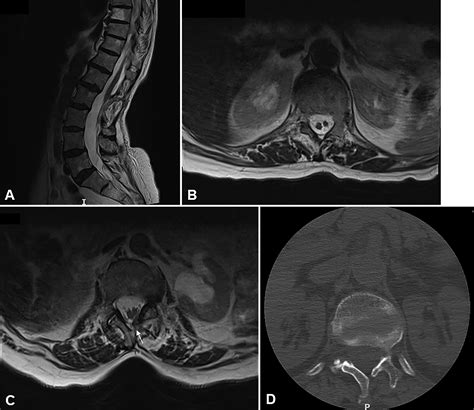

Tethered Cord MRI plays a pivotal role in the diagnosis of tethered cord syndrome. This imaging technique uses magnetic fields and radio waves to produce detailed images of the spinal cord and surrounding structures. Unlike traditional MRI, Tethered Cord MRI focuses specifically on the spinal cord, providing high-resolution images that can detect even the slightest abnormalities.

One of the key advantages of Tethered Cord MRI is its ability to visualize the spinal cord in multiple planes. This allows radiologists to get a comprehensive view of the spinal cord and identify any areas where it may be tethered. The images obtained from Tethered Cord MRI are also highly detailed, making it easier to pinpoint the exact location and extent of the tethering.

After the Tethered Cord MRI procedure, the images will be reviewed by a radiologist who specializes in interpreting MRI scans. The radiologist will look for signs of tethered cord syndrome, such as:

• Abnormal Attachments: The spinal cord may be attached to surrounding tissues, such as the dura mater or vertebrae, in an abnormal manner.

• Thickened Filum Terminale: The filum terminale is a thin, fibrous structure that anchors the spinal cord. In tethered cord syndrome, this structure may be thickened or shortened.

• Spinal Cord Stretching: The spinal cord may appear stretched or elongated, indicating that it is being pulled down by the tethering.

• Other Abnormalities: The radiologist may also look for other abnormalities, such as spinal cord tumors, cysts, or malformations, that could be contributing to the symptoms.